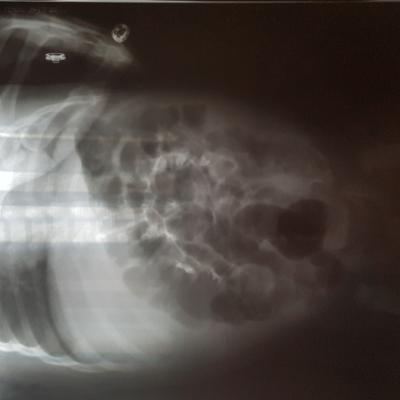

Болезнь Ормонда (ретроперитонеальный фиброз, забрюшинный фиброз) – хроническое воспаление жировой клетчатки забрюшинного пространства, которое постепенно приводит к компрессии и нарушению проходимости трубчатых структур данного анатомического участка. Чаще всего, в качестве этих тубулярных структур выступают мочеточники.

У меня есть сомнения, что причиной гидронефроза в Вашем случае явилось именно это состояние.

Возможно речь идет о пузырно-мочеточниковом рефлюксе.